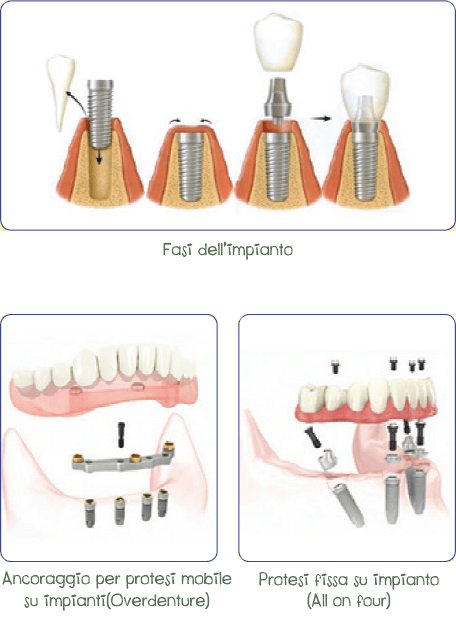

L’implantologia è la parte dell’odontoiatria che si occupa della sostituzione dei denti mancanti con gli impianti, i quali possono essere utilizzati per sostituire un singolo dente o come pilastri per ponti fissi o, ancora, per l’ancoraggio di protesi mobili.

Gli impianti dentali sono delle viti di titanio che vengono inserite nell’osso della mandibola o della mascella per sostituire denti mancanti o stabilizzare delle protesi mobili.

Con un processo detto osteointegrazione, il tessuto osseo si lega intimamente all’impianto: questo avviene in un periodo di circa due o tre mesi. Trascorso questo periodo, l’impianto può essere utilizzato, a seconda del caso, per sostituire uno o più denti o come supporto per protesi mobili.

Gli impianti si inseriscono tramite un piccolo intervento chirurgico normalmente eseguito nello studio dentistico; nei giorni immediatamente successivi possono seguire alcuni disturbi facilmente controllabili nella parte operata, quali leggero dolore e gonfiore.

In anestesia locale si procede ad incidere la gengiva per esporre l’osso nel quale viene eseguito un foro per posizionare l’impianto prescelto. Dopo aver posizionato l’impianto la gengiva viene suturata.

L’implantologia spesso rende possibile la realizzazione di una protesi fissa.

Tuttavia quando ciò non è possibile, inserire degli impianti serve come ancoraggio alla protesi mobile, fornendo maggior stabilità e comfort nel parlare, nel masticare e nel sorridere.